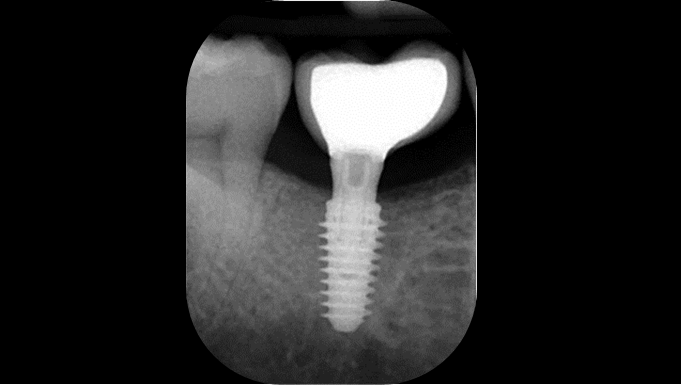

Clinical case: # 46 implant placement & GBR using i-Gen membrane for significant vertical resorption & mixed bone defect

AnyRidge, mandibular posterior, i-Gen, resorption, bone defect, bone regeneration, space management, #46, GBR, Dr. Iulian Filipov

“AnyRidge KnifeThread achieves excellent stability in regenerated bone & even in only 3mm bone height!”